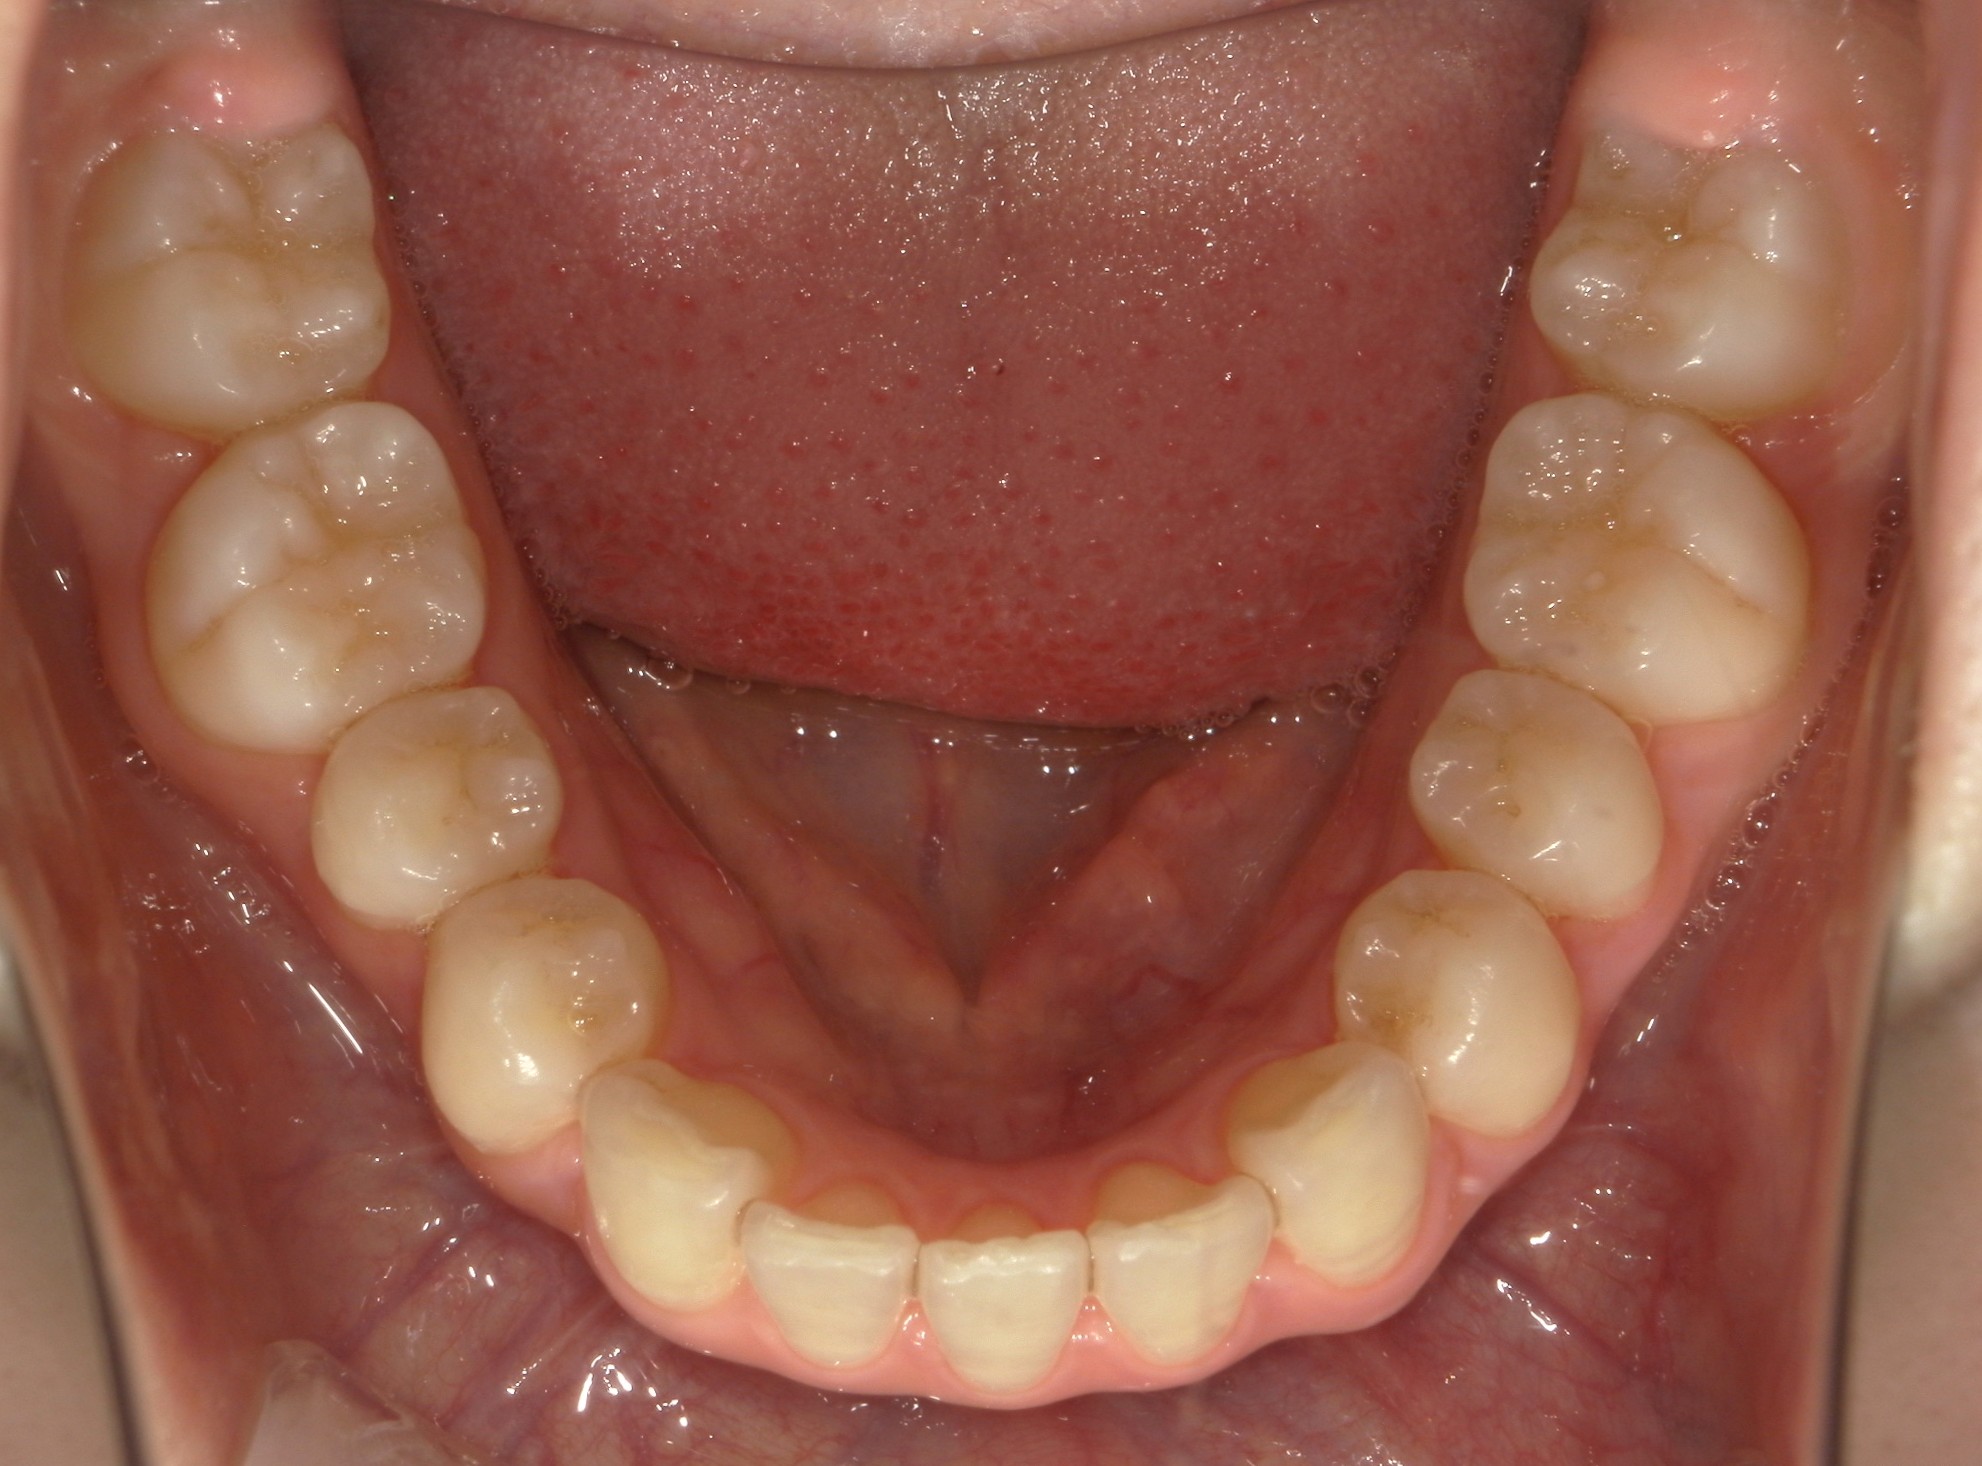

口内下

治療前

治療後

横から見た口腔内写真でよくわかるように、前歯が出っ歯になっており、全く咬んでいない状態でした。また下の前歯が本来4本あるところが、先天的に一本少なく3本しかない(Three incisors)であったため下顎のアーチが小さいというお口の状態でした。前歯を正しい傾きに治し、咬合させるため、上の歯のみ2本の抜歯を行うこととしました。下の前歯が3本のため、その正中に注意しながら前歯の傾きを修正し、奥歯のポジションを整えて仕上げました。口元の突出感は大きく改善し、咬合も良好な状態で完了することができました。